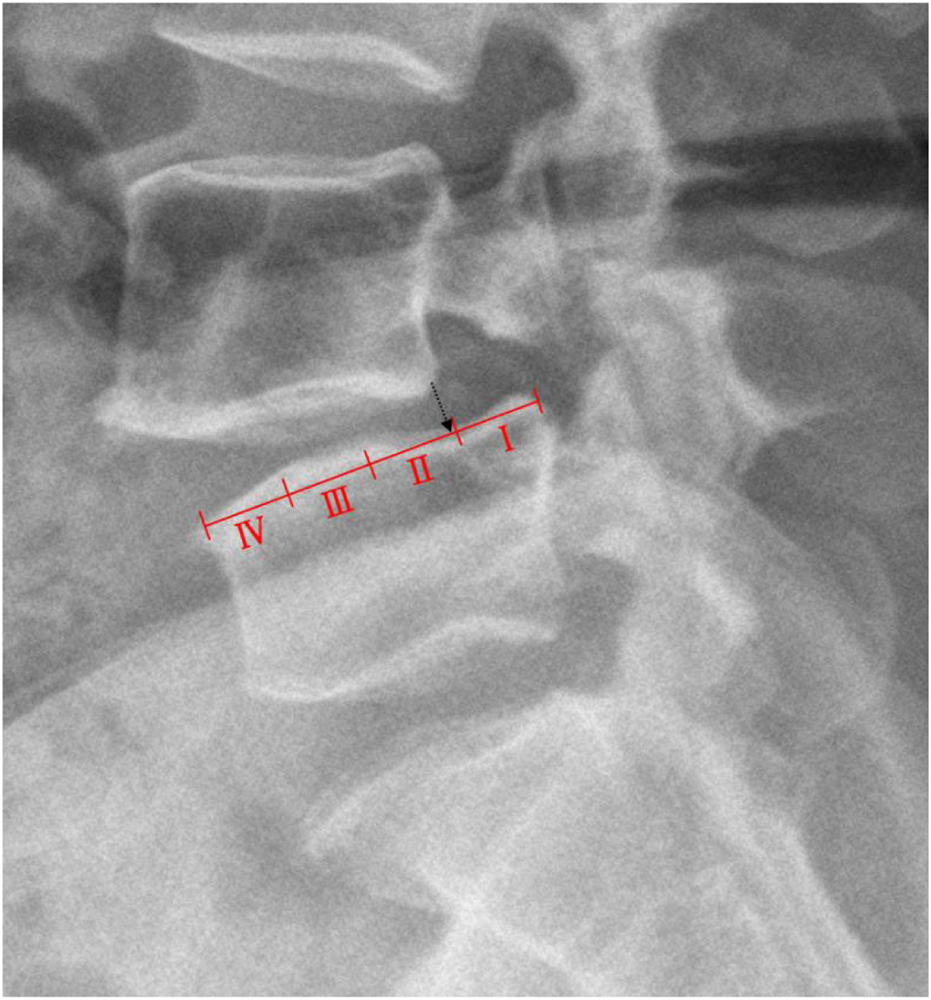

The classification of lumbar spondylolisthesis is divided into 4 grades according to the Meyerding classification method (Tumialan, 2019). The anterior-posterior diameter (AP) of the upper surface of the lower vertebral body is divided into four equal parts, degree I is within 1/4, degree II is between 1/4 and 2/4, degree III is between 2/4 and 3/4, while over 3/4 is graded IV (Figure 2).

FIGURE 2

Schematic diagram of the Meyerding classification measuring method.